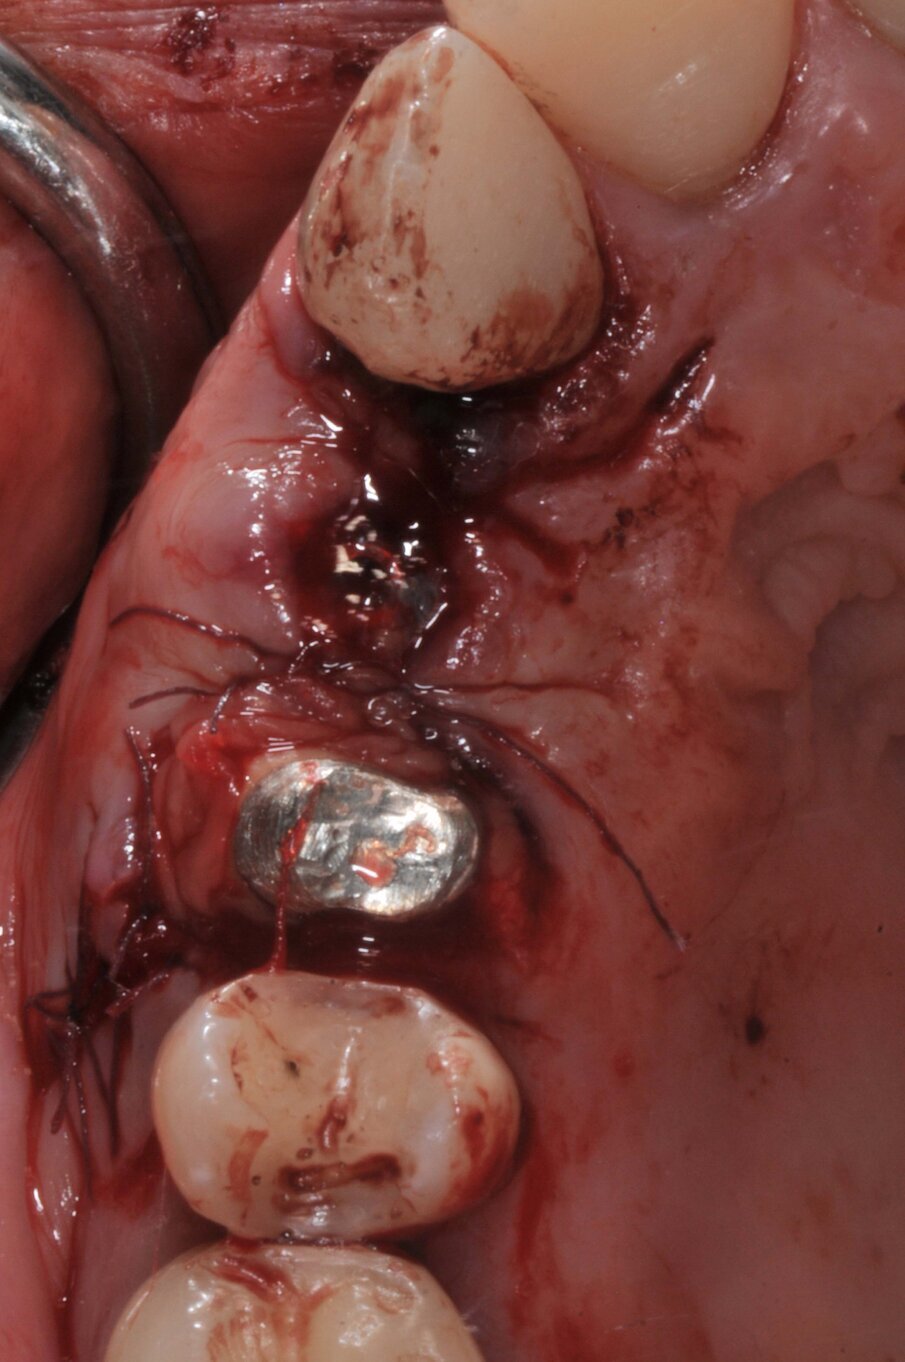

Le corone sui denti 1.3 e 1.4 furono rimosse, il dente 1.3 fu estratto e l’alveolo fu riempito con una membrana di PRGF ottenuta tramite centrifugazione del sangue della paziente con il sistema Endoret e un provvisorio fu consegnato sui denti 1.3 e 1.4 (Fig. 5, 6). Dopo otto settimane fu eseguita una nuova cone-beam e la chirurgia fu pianificata (Fig. 7). Si eseguì un lembo a tutto spessore, fu eseguita l’osteotomia e fu inserito un impianto BTI Core 3.5 × 8.5. Un pilastro Unit fu avvitato e un tappo di guarigione fu applicato. L’osso ottenuto dalla fresatura mescolato con una membrana di PRGF fu applicato sul lato palatale per compensare una piccola deiscenza, una seconda membrana fu applicata sopra l’osso circostante e un innesto di tessuto connettivo prelevato dalla tuberosità fu suturato vestibolarmente per ricreare la bozza canina. Punti di sutura staccati furono eseguiti con un filo in PTFE (Figg. 8-11). Dopo quattro mesi il provvisorio fu rimosso e i tessuti apparivano sani e con un buon spessore di tessuto connettivo vestibolare per garantire la stabilità nel tempo del risultato. Fu eseguita un’impronta con la tecnica del cucchiaio aperto e dopo due settimane furono consegnate una corona in zirconio cementata sul dente 14 ed una avvitata sul denta 1.3. Il profilo di emergenza della corona sull’impianto appariva ideale. Purtroppo, a causa della mancanza del picco osseo sul versante distale del dente 1.2, non si ottenne una papilla di altezza adeguata. Ciononostante la paziente si disse soddisfatta del risultato e rifiutò ulteriori terapie per correggere il difetto residuo (Figg. 12-15).